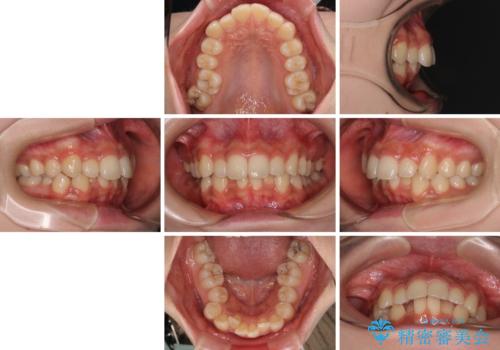

- 上顎前歯の突出感を気にして来院された患者様です。

上下左右第一小臼歯4本を抜歯して、積極的に口元を引っ込めるよう、ワイヤー装置にて矯正治療を行うこととしました。